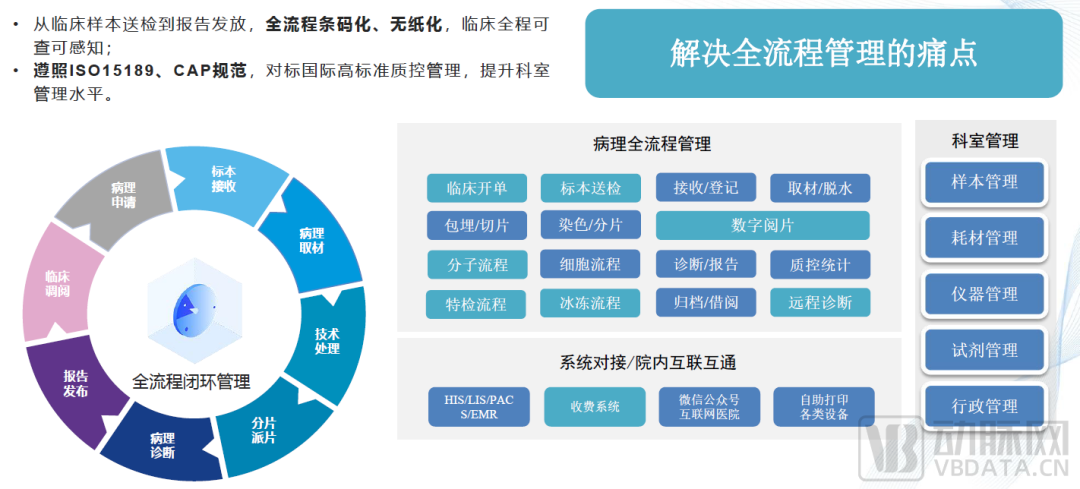

工作流程对比图

工作流程对比图

来源:商汤科技